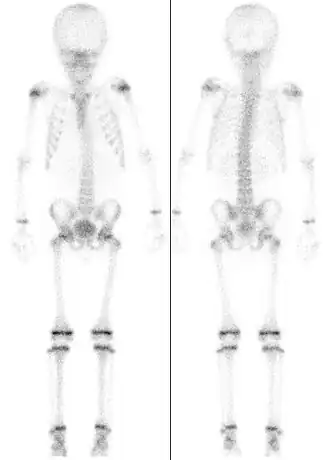

![]() Сцинтиграфия скелета семилетнего ребёнка, демонстрирующая интенсивный обмен в зонах роста. | |

Эпифизарная пластинка (хрящевая пластинка роста) или зона роста — пластинка гиалинового хряща между эпифизом и метафизом трубчатых костей. Эпифизарная пластинка отмечается у детей и подростков; у взрослых её нет; после окончания роста она замещается эпифизарной линией.

Зона роста — участок растущей ткани с обоих концов длинных трубчатых костей у детей и подростков. От её роста зависит будущая длина и форма зрелой костной ткани. После завершения роста в конце пубертатного возраста (для каждой кости имеется свой возраст закрытия этих зон) рост их завершается, и зона роста замещается твёрдой костной тканью.